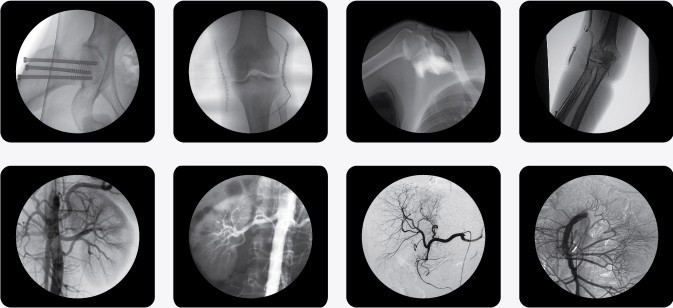

廣泛應(yīng)用于 介入科、骨科、外科、矯形外科、泌尿外科、脊柱外科、腹部外科、疼痛科、心臟科、消化科、婦科及手術(shù)室等。

三、C型臂X光機(jī)PLX7000B數(shù)字高清影像,支持您做出精確診斷

·全數(shù)字化百萬像素影像采集系統(tǒng),優(yōu)化設(shè)計(jì)和配置,為您提供高分辨率、高灰階圖像,支持您做出精確診斷。

1、內(nèi)置先進(jìn)圖像自動(dòng)優(yōu)化處理、增強(qiáng)模塊,實(shí)時(shí)顯示自動(dòng)優(yōu)化后的清晰臨床影像。

2、專業(yè)的影像處理工作站具備窗寬窗位調(diào)節(jié)、自動(dòng)伽瑪校正、興趣點(diǎn)、反相、降噪、平滑、銳化等豐富且強(qiáng)大影像處理功能,帶給您更強(qiáng)大的診斷信心。

·專用高清醫(yī)用液晶顯示系統(tǒng),呈獻(xiàn)給您高亮度、高對(duì)比度的臨床圖像;對(duì)比自然,有益于診斷的圖像細(xì)節(jié)顯示更加清晰、層次更加豐富